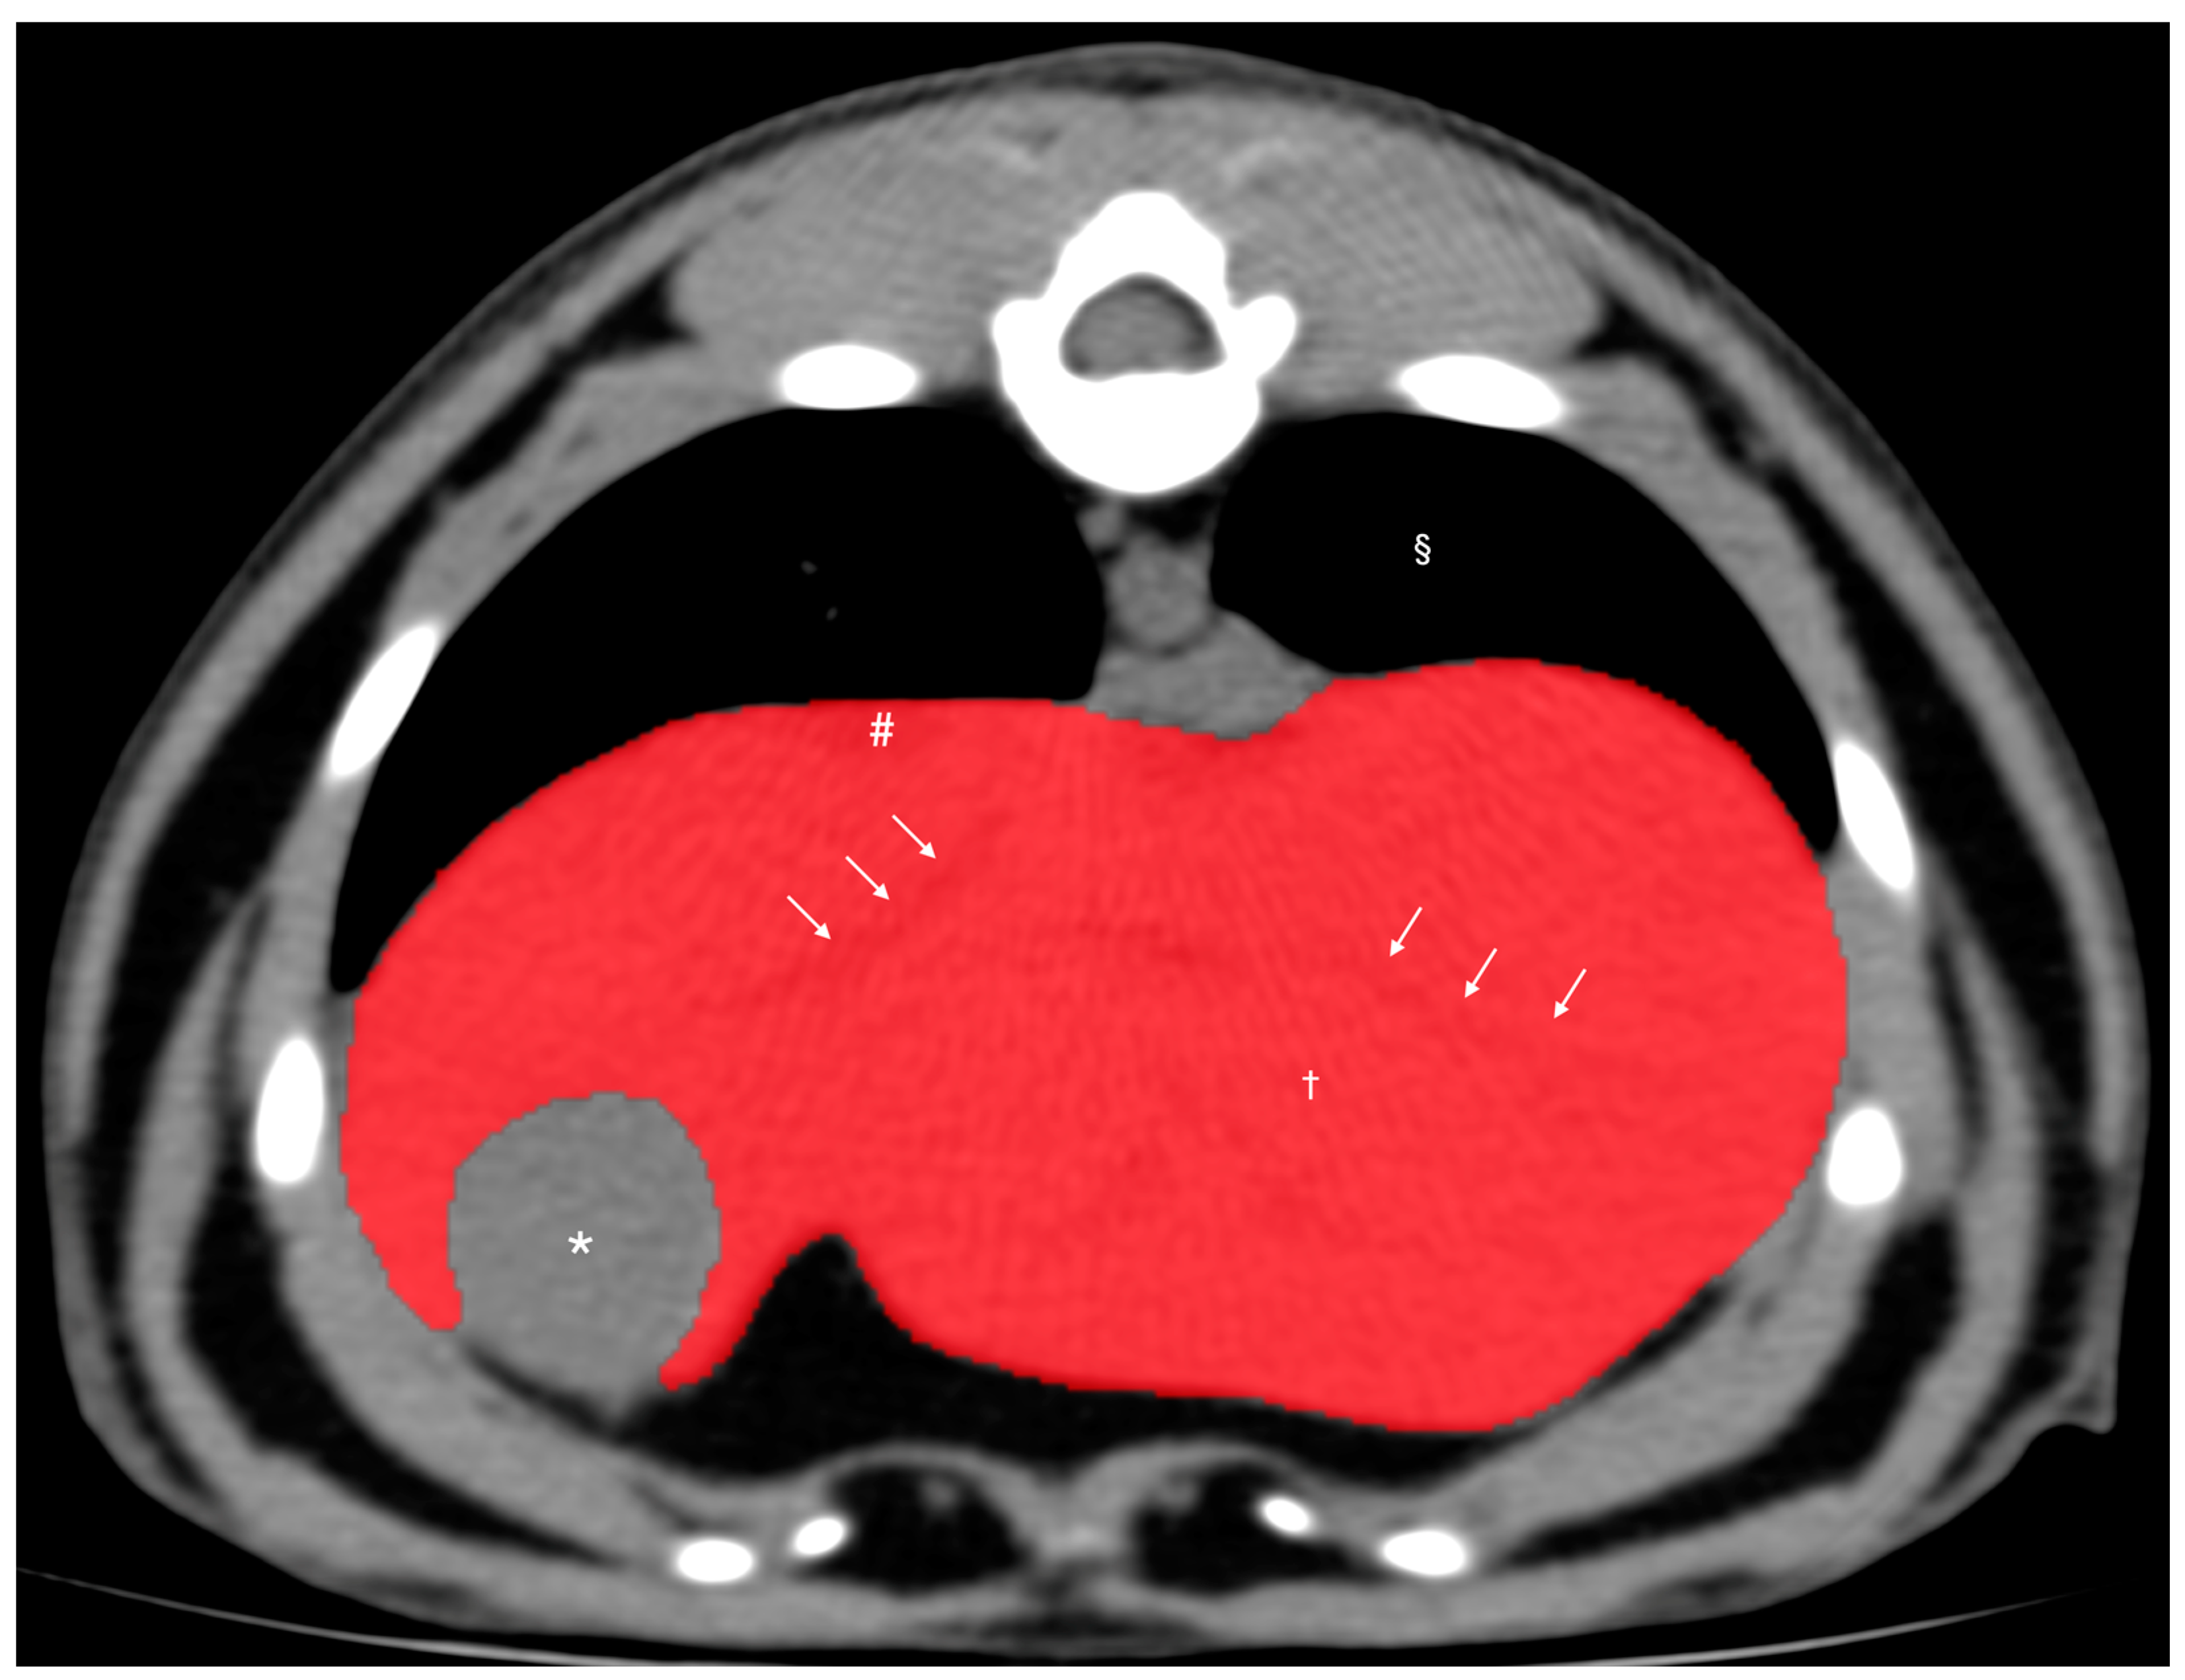

2.3. Computed Tomographic Hepatic Volumetry (CTHV) Analysis